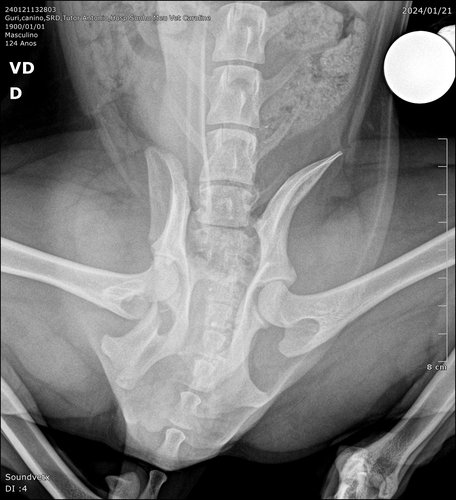

Estou aos cuidados da Dona Malu e alguns vizinhos do Condomínio Vivaz santa Fé esta me ajudando com carinho e doações de remédios. Preciso realizar uma cirurgia pois estou com múltiplas fraturas no fêmur.

Orçamento cirurgia Guri

R$ 1.380 - estabilização de fratura de ílio direito + estabilização de disjunção sacroilíaca esquerda (material ortopédico incluso).